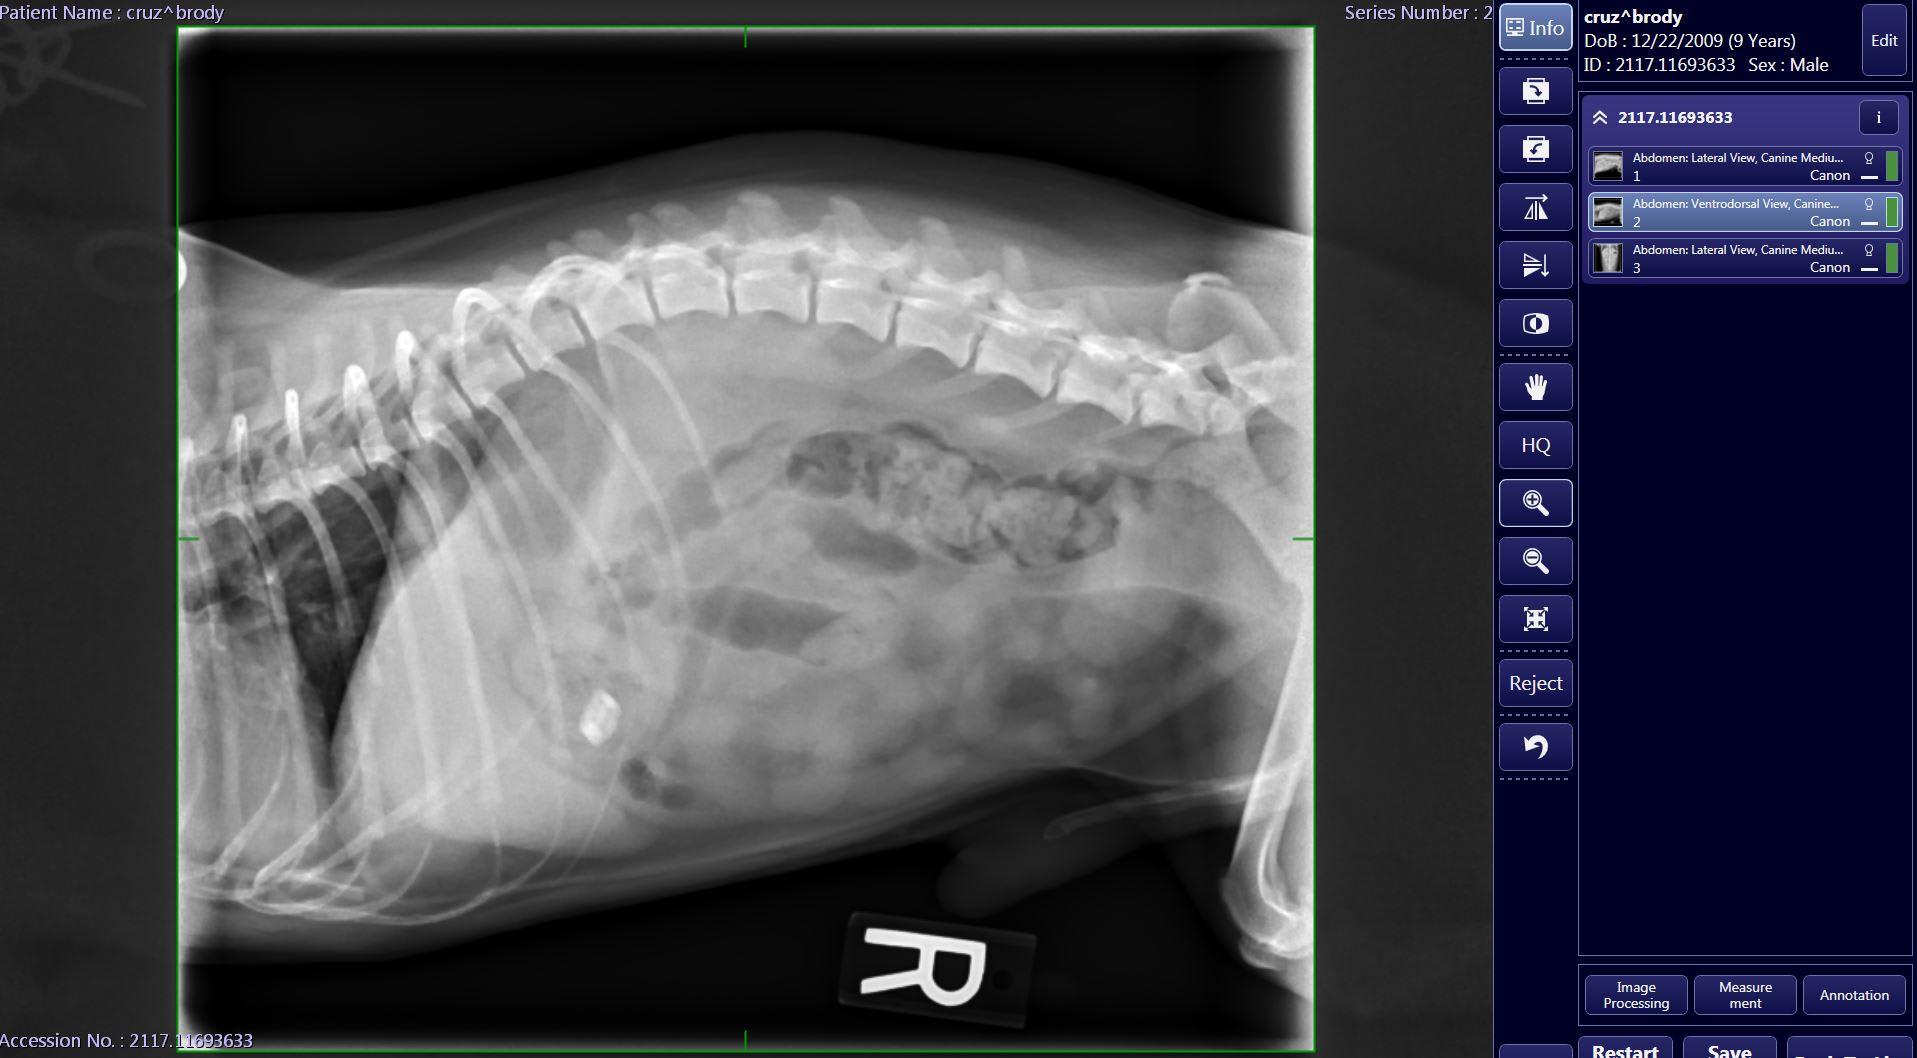

my dog Swallowed a small piece of wrapper from a salami that has a small metal piece attached on 12/18. He started throwing up yellow bile for about four days I took him in on Saturday for x-rays which showed the object still in his stomach. He has been acting normal, he eats, drinks water he goes on walks and pees/poops fine but the object has not moved from the stomach after I took him to the vet once again this Monday, 12/24. Vet recommended to wait till Jan 2 but I’m afraid that’s too long.